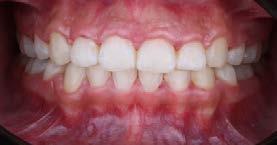

Estudio comparativo, observacional y experimental in vivo. Se empleó en una paciente femenina de 56 años de edad; valorada en la clínica de rehabilitación oral del Centro de Estudios Multidisciplinario de Rehabilitación Oral, (CEMRO), en Tarímbaro, Michoacán; quién decidió hacer un cambio en su sonrisa debido a que esta le generaba insatisfacción, cambiando sus restauraciones antiguas, deficientes en el sector anterior; para lo cual se planeó el retiro de 5 coronas de metal-porcelana de los OD 11,12, 13, 21 y 22 vitales, las cuales serán confeccionadas mediante técnica CAD/CAM realizando su historia clínica y autorizando su consentimiento informado.

Se planteó la utilización de cerámica feldespática e-max de la casa comercial Ivoclar Vivadent, en la presentación de bloques para la realización de las coronas totales en los OD

11, 12 y 13 mediante técnica CAD/ CAM, en su versión HT, color A2. Por otro lado, las otras 2 coronas de los OD 21 y 22 fueron confeccionadas con disco de zirconia Zahndent en tono A2. Estas fueron puestas a prueba mediante la aplicación Adobe Photoshop, con ayuda de una fotografía de las coronas tomada antes de su cementación definitiva, y una segunda medición con las coronas ya cementadas, únicamente se realizó el análisis en los OD 11 Y 21, los cuales fueron cementados con cemento translucido Multilink Speed de Ivoclar Vivadent, se tomaron fotografías con cámara profesional Cannon T8 y lente macro 100mm. Es importante mencionar que decidí utilizar cemento dual translucido para evitar alteración en el color de las coronas ya cementadas, con el fin de obtener mediciones puntuales de color y determinar las cantidades de pigmento que hay en cada corona mediante un fondo negro y así poder corroborar que se logró un buen mimetismo. El tiempo estimado para el procedimiento fue de 5 citas.

Figura 1. Coronas antes de su cementación (Francisco Javier Méndez Landa 2024).

porcentaje de 0 a 100, obteniendo el porcentaje exacto de cada uno de esos colores, que una vez mezclados obtenemos el tono real de las coronas (Figura 1).

Se realizó la medición del color de las coronas mediante una fotografía en formato RAW en fondo negro (Figura 2).

Se muestra un análisis del proceso de medición de color de las coronas antes de su cementación y cómo se obtuvieron los resultados, mediante la aplicación Adobe Photoshop (Figura 3).

Se muestra una fotografía del análisis de los incisivos centrales, los cuales fueron confeccionados: el órgano

dentario 11 con disilicato de litio y el órgano dentario 21 con zirconio.

Resultados

Los resultados obtenidos fueron que, en promedio, sí existe variación de los pigmentos en cuanto a la medición de la mezcla de los 3 colores antes de ser cementadas las coronas del canino, incisivo central y lateral superior derechos; las cuales fueron confeccionadas con e-max, en una escala de 0 a 255 que arroja la aplicación Adobe Photoshop obteniendo los siguientes valores: en cuanto al canino superior derecho, se obtuvieron valores del color rojo: 195, del color verde: 179 y del color azul: 157. Del incisivo lateral izquierdo superior se obtuvo del color rojo: 197, del color verde: 181 y del color azul 161. Del incisivo central superior izquierdo se obtuvo del color rojo: 195, del color verde: 180 y del color azul: 158. En

cuanto las otras 2 coronas restantes, las cuales fueron confeccionadas con zirconio del incisivo central superior derecho obtuvimos del color rojo: en promedio 196, del color verde: 181 y del color azul: 161. Del incisivo lateral superior derecho del color rojo obtuvimos: 187, del color verde: 174 y del color azul: 156.

Se realizó un segundo análisis con las coronas ya cementadas en boca, únicamente de los incisivos centrales superiores, ya que uno fue confeccionado con disilicato de litio y el otro con zirconio. En este caso obtuvimos como resultado en la corona de disilicato de litio: del color rojo: 172, del color verde: 148 y en cuanto al color azul: 123. En la corona de zirconio obtuvimos del color rojo: 171, del color verde: 143, y del color azul: 119; en la escala de 0 a 255 que arroja la aplicación de Adobe Photoshop.

Podemos afirmar que también hubo variación y a pesar de utilizar 2 tipos de cerámicas diferentes, se logró obtener un buen mimetismo, dando como resultado un resultado satisfactorio para la paciente.